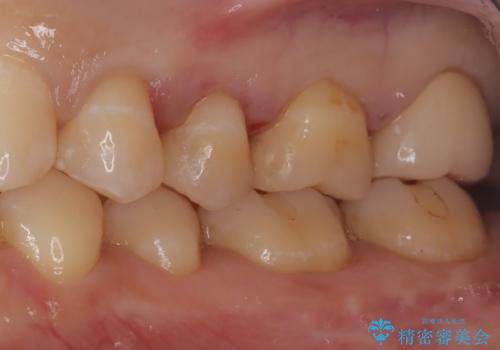

【セラミックインレー】虫歯の治療

- 定期検診にて虫歯を認めたため、セラミックインレーにて治療を行いました。

治療時にはラバーダムを装着しております。